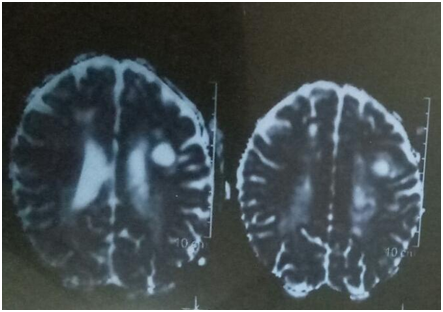

In our case the MRI was one of most benefit tool to differentiate between the two conditions as there periventricular distribution together with picture of enhancement lesions and venous enhancement was characteristic of vasculitis as shown in Figure 3 so in the context of bechet disease, the diagnosis of neurobehcet with cerebral activity was confirmed.

Figure 3 MRI brain.